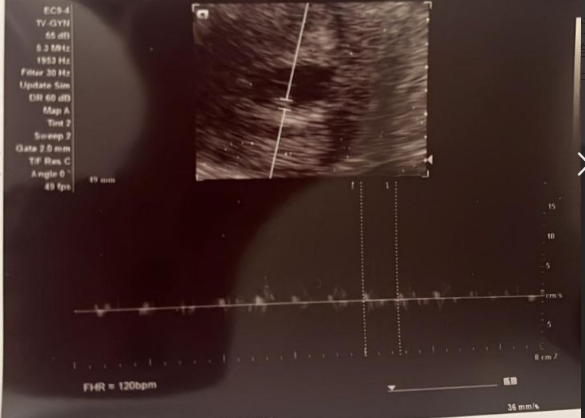

恭喜啦!9月15日複查順利見胎心,孕6週+5天,寶寶心跳穩定在114次/分(美國線),一切進展良好,繼續安心養胎哦~

9月6日做B超查胎心,當日為孕6週+3天,B超報告:已見胎心,頭臀長0.57cm,胎心116bpm,恭喜順利見胎心!